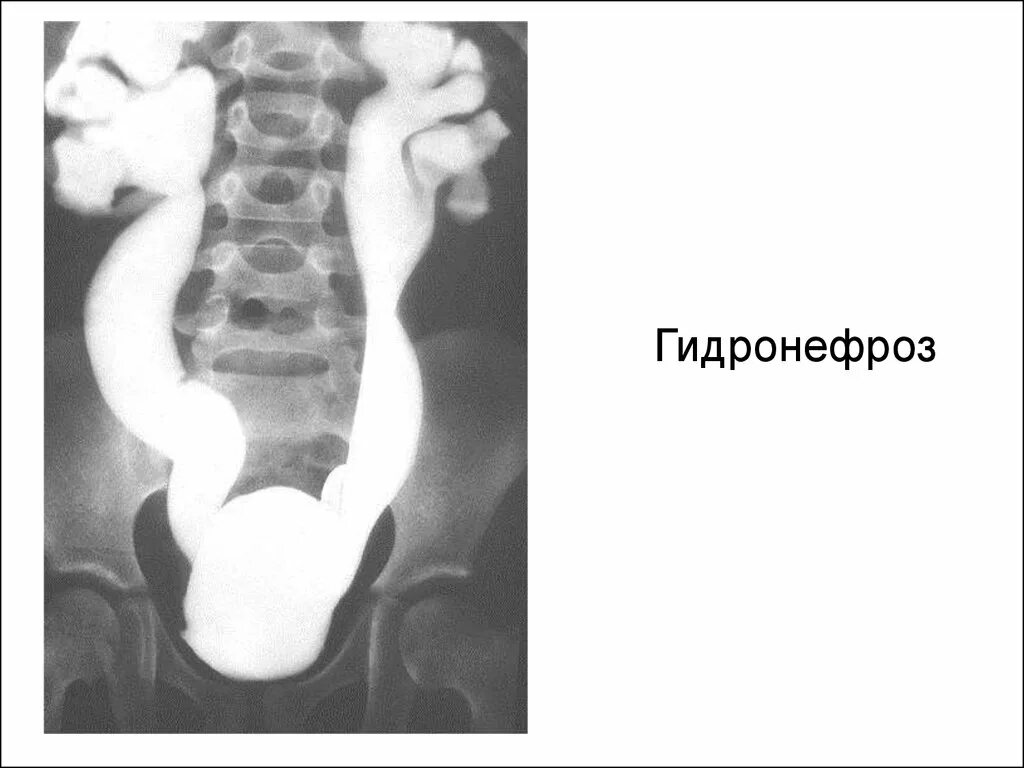

Мегауретер у детей что это